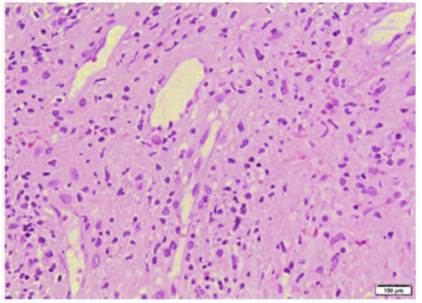

Figura 4 Biopsia de piel en palma de mano. En la dermis superficial tuvo edema, telangiectasias y extravasación de eritrocitos. Se identificaron infiltrados linfoides perivasculares con linfocitos que permeaban la pared de vasos sanguíneos y evidencia de reactividad endotelial, pero sin necrosis. Tinción hematoxilina-eosina.